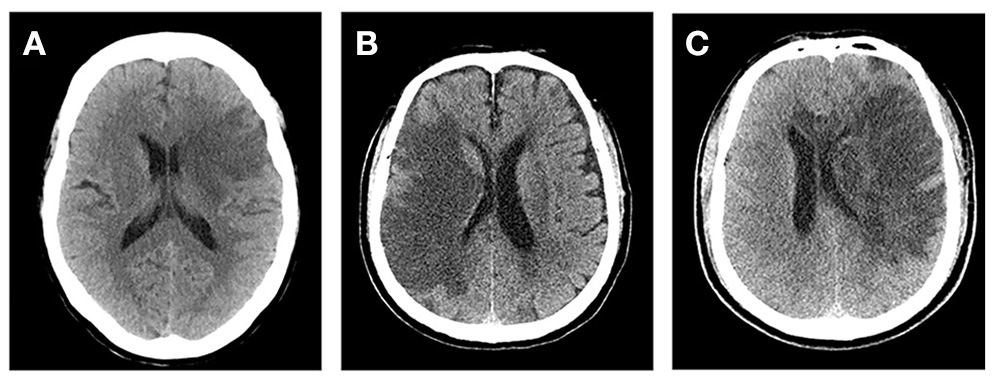

At present, several comprehensive scores are based on the above methods, such as cerebral edema grading (grade 1 = focal brain swelling of ≤ 1/3 of the hemisphere, grade 2 = >1/3 of the hemisphere, grade 3 = edema with MLS; Figure 1). These scores are used widely in clinical studies (43–45). However, this semi-quantitative method can only be applied to roughly assess the degree of edema, and it is insufficient for evaluating patients with mild edema.

Figure 1

Cerebral edema grades. (A) Left frontal lobe and basal ganglia brain swelling, <1/3 of the hemisphere. (B) Right frontal and parietal lobe brain swelling, >1/3 of the hemisphere and without midline shift (MLS). (C) Left cerebral hemisphere swelling, >1/3 of the hemisphere with MLS.